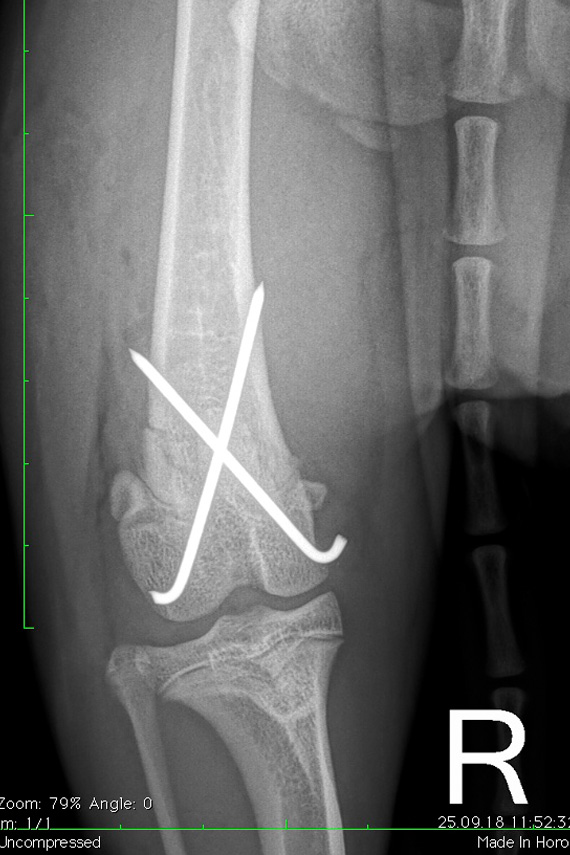

Salter Harris Fraktur

Wachstumsfugenfraktur (Salter Harris Fraktur) am distalen Femur bei einem Hund

Versorgung der Fraktur mit Pins